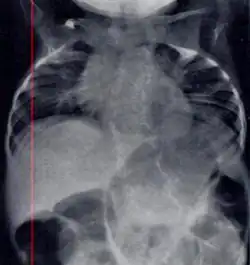

Characteristic radiograph from child with Jarcho-Levin syndrome, spondylocostal dysostosis subtype

In contrast to STD, the subtype spondylocostal dysostosis, or SCD features intrinsic rib anomalies, in addition to vertebral anomalies. Intrinsic rib anomalies include defects such as bifurcation, broadening and fusion that are not directly related to the vertebral anomalies (such as in STD, where extensive posterior rib fusion occurs due to segmentation defects and extreme shortening of the thoracic vertebral column).[6] In both subtypes, the pulmonary restriction may result in pulmonary hypertension, and have other potential cardiac implications.[7]